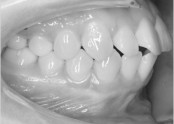

• 치아교정 돌출입 교정

• 치아교정 덧니 교정